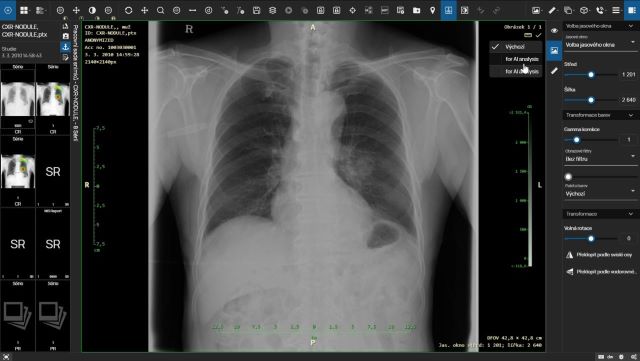

AI má v dnešnej dobe využitie v rôznych oblastiach. Napríklad pri diagnostike pľúcnych ochorení ako je edém či tuberkulóza môžu pomôcť riešenia vyhodnocujúce röntgen pľúc, iné AI riešenia, ktoré sú schopné vyhodnocovať CT pľúc, môžu byť nápomocné pri identifikácii pľúcnych nodulov, teda oblastí značiacich prvopočiatok malígneho ochorenia. Röntgen končatín je možné zanalyzovať pomocou AI a identifikovať tak fraktúru, dislokáciu alebo kĺbny výpotok. Analýza CT mozgu s využitím AI zase pomôže s diagnózami ako je fraktúra lebky či krvácanie. Ďalšie uplatnenie AI nájdeme v mamografii pri detekcii a klasifikácii mikrokalcifikácií alebo hodnotení hustoty pŕs pomocou stupnice BI-RADS. Rovnako je možné využiť AI pri príprave merania – klasifikácia skoliózy, náklon pánvy, dysplazia bedrového kĺbu. V oftalmológii vie AI pomôcť s diabetickou retinopatiu, glaukomom (zeleným zákalom) či vekom podmienenou makulárnou degeneráciou (AMD). Dôležité vo všetkých prípadoch je, aby využívané riešenia boli certifikované ako zdravotnícky prostriedok a odpovedali novému nariadeniu o zdravotníckych prostriedkoch MDR.

Zamýšlali ste sa nad tým, kde je vlastne AI inštalovaná, keď ju chce nemocnica využívať? Väčšina dodávateľov umožňuje oba spôsoby, teda inštaláciu on-premise (tj. vo vlastnej infraštruktúre nemocnice) aj inštaláciu v cloude, pričom práve cloudy sú využívanejšie. Zároveň ale platí aj to, že cloudy sú zraniteľnejšie. V tomto prípade je treba dbať na zvýšenú bezpečnosť, šifrovanie komunikácie a anonymizovanie dát, ktoré opúšťajú prostredie nemocnice. Zároveň by malo byť dané riešenie AI umiestnené v cloude v rámci Európskej únie. Pri výbere AI je dobré sa uistiť, či výrobca svoje riešenie penetroval a realizoval skúšky s cieľom identifikovať zraniteľnosti svojho systému voči útoku hackerov. Samostatnú kapitolu tvoria aj inštalácie AI do prostredia nemocnice štýlom „tak, ako prídu“, niektoré AI môžu byť využívané na modalite, iné sú do nemocnice nainštalované samostatne bez súčinnosti dodávateľov aktuálne využívaných nemocničných systémov a bez integrácie do jednotného používateľského prostredia. Nemocnice by sa teda mali brániť nekoordinovanému zavádzaniu rôznych AI technológií od rôznych dodávateľov a mali by k tejto problematike pristupovať systematicky a s ohľadom na bezpečnosť pacientskych dát. Výsledky analýz rôznych AI by sa naviac mali používateľom zobrazovať jednotným spôsobom bez ohľadu na to, z akej umelej inteligencie pochádzajú. Ideálnym východiskom z tejto situácie je integrovať riešenia AI do jedného systému, napríklad PACS (systému na archiváciu a zobrazovanie obrazovej dokumentácie), s ktorým pracuje každý rádiológ. Výhodou tohto konceptu je, že komunikáciu s cloudami a riešeniami AI potom zabezpečuje jeden systém z nemocnice a používateľ pracuje s jedným systémom, resp. jedným prostredím. Výsledky rôznych dodávateľov AI sú tak tiež zobrazované pre používateľa v jednotnej forme.